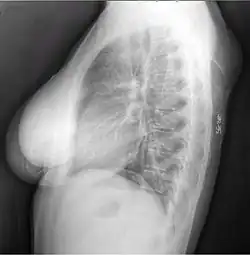

A physical exam is typically the easiest way to diagnose it. Rarely, a tissue biopsy or imaging may be required. The imaging modality of choice is magnetic resonance imaging (MRI) because it has superior sensitivity of distinguishing it from liposarcoma as well as mapping the surrounding anatomy.[22]

-

X-ray of a lipoma -

X-ray showing lipoma -